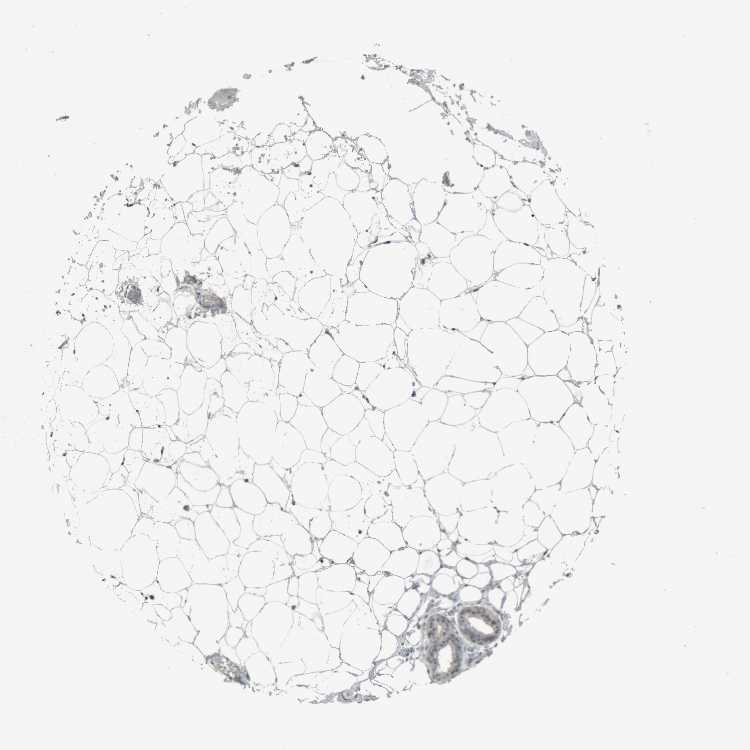

SOFT TISSUE 2 - Antibody stainingi

Antibody staining in the annotated cell types in the current human tissue is reported as not detected, low, medium, or high, based on conventional immunohistochemistry profiling in selected tissues. This score is based on the combination of the staining intensity and fraction of stained cells.

Each image is clickable and will lead to virtual microscopy that enables deeper exploration of all samples and also displays staining intensity scores, fraction scores and subcellular localization as well as patient and tissue information for each sample.

Antibody HPA024642

Chondrocytes Not detected

Fibroblasts Low

Peripheral nerve Not detected